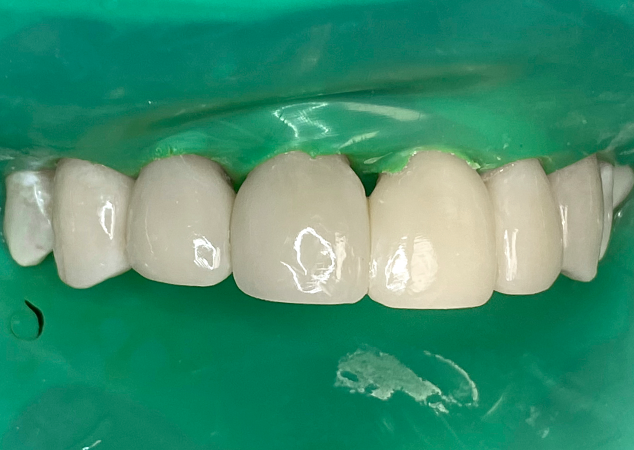

Toutes les dents restantes sont ensuite traitées une par une avec les matrices Bioclear Black Triangle de taille appropriée (Fig. 7), puis moulées par injection et réduites séquentiellement, selon les mêmes principes (Fig. 8).

FIG. 8

La réduction finale est obtenue une fois que toutes les dents du sextant 2 sont moulées par injection.

Les étapes de mise en forme finale, de prépolissage et de polissage final sont effectuées à l'aide de disques grossiers 3M Sof-Lex, de Bioclear Magic Mix et de la cupule de polissage Bioclear Rockstar séquentiellement (Fig. 9). Au cours de la phase initiale de réduction, la fraise diamantée conique grossière Komet laisse des stries dans le composite. Le disque grossier 3M Sof-Lex vise à lisser les rayures et à préparer les surfaces pour le prépolissage. Il convient d'être très vigilant à ce stade pour identifier tout vide, défaut ou bulle d'air potentiel qui pourrait apparaître. Des corrections, ou augmentations selon la terminologie Bioclear, doivent être effectuées à ce stade et avant l'introduction de contaminants de surface pendant le processus de polissage. La pâte Bioclear Magic Mix est ensuite appliquée sur le composite et travaillée dans la surface à l'aide d'une cupule de prophylaxie jetable blanche. Il est préférable d'utiliser une vitesse lente à air et de faire pulser le mélange sur la surface de la dent afin d'engager les différentes tailles de grains de diamant et de particules d'oxyde d'aluminium présentes dans la pâte. Le Bioclear Magic Mix agit agressivement sur le composite mais est doux pour l'émail. Cette étape de prépolissage laisse les facettes en composite avec une surface mate et uniforme qui est prête à être polie avec la cupule imprégnée de diamant Bioclear Rockstar RS Polisher.

FIG. 10

Radiographies périapicales pré et post-opératoires.

Une fois la digue en caoutchouc retirée, les embrasures incisives sont réexaminées pour une mise en forme finale. Des radiographies périapicales postopératoires sont prises pour confirmer l'absence d'excès de restauration sous-gingival (Fig. 10). Remarquez les courbes généreuses obtenues grâce au contour anatomique des matrices pour triangles noirs Bioclear. (Fig. 11)